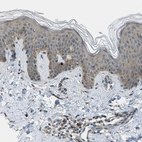

Immunohistochemical staining of human urinary bladder shows strong cytoplasmic positivity in urothelial cells.